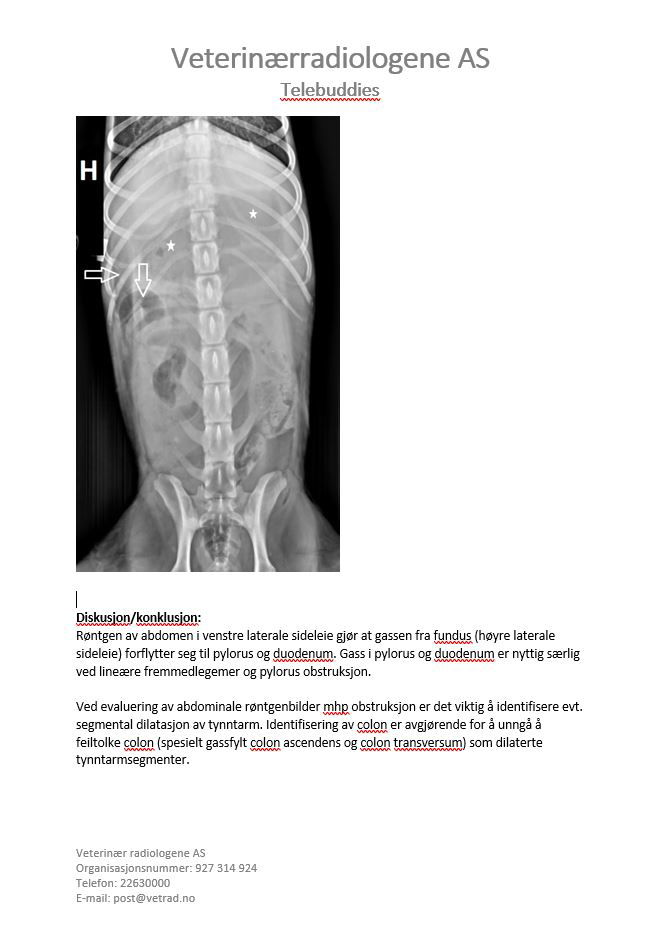

Signalement: Portugisisk vannhund, tispe, 2 år. Anamnese: Oppkast i 2 dager, stort sett uproduktive brekninger siste døgnet. Ingen matlyst eller avføring i disse dagene. Hadde mageproblemer for 2 uker siden, trolig fått i seg pinnekjøtt da. Nedstemt ved ankomst klinikk. Ingen informasjon om siste løpetid.